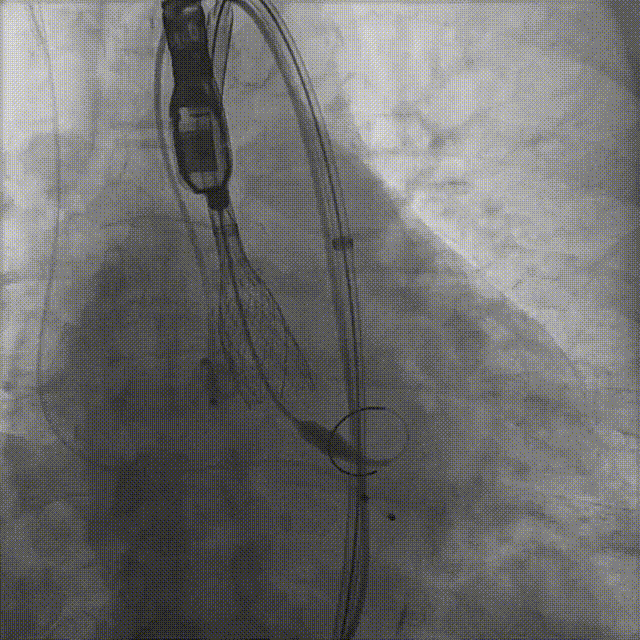

患者病史 男性,74y, 因 “发现心脏瓣膜病 1 年,加重伴喘气半年” 入院。门诊检查显示主动脉瓣重度AS并伴轻-中度AR。患者基础疾病较多:胸腹主动脉多发穿透性溃疡、心功能III级等,手术指征明确,但风险极高。 术前CT LVOT- Annulus 倒梯形,对植入瓣膜有挤压位移风险,Annulus直径23.7mm,瓣叶增厚,钙化集中在无冠窦边缘。 左冠脉开口高度可,瓣叶不长、窦部空间较大,无冠脉风险;室间隔膜部较短,有一定PPI风险,心脏角度37.9°;心室较小,有一定循环崩溃风险,术前注意补液。 术前造影角度及入路:血管入路散在钙化、无迂曲;主动脉弓条件好、双侧股动脉直径大、右股穿刺点侧壁存在环形钙化 左右重合位:RAO 7° CAU 21° 右窦中心位:LAO2 1° CAU 1° 手术策略 20mm球囊预扩后植入AV26瓣膜,同时做好预防循环崩溃、传导阻滞的应急预案。 术中挑战 1)球囊预扩:20mm球囊预扩时无明显 “腰征”,但存在少量反流,提示瓣膜钙化与解剖结构对扩张的阻力不均 2)首次释放偏差:第一次定位释放时,瓣膜在 “开花” 过程中下滑约 3mm,工作位观察显示小弯侧瓣周漏较多(深度超过完全覆膜区),需二次调整。 3)二次精准定位:以猪尾导管为参照,将定位点调整至 “猪尾 - 2mm” 处,结合真实窦底深度(较深)重新释放,最终瓣膜位置稳定,瓣周漏显著减少。 术后即刻效果: 瓣膜形态良好,跨瓣压差从术前的 67mmHg 降至 6mmHg,且无明显瓣周漏,冠脉开口通畅; Commisural Alignment 术后即刻超声: Prostyle A®预装干瓣——助力临床最优化解决方案: √ 平衡的径向支撑力:特殊的解剖结构下位置形态良好,术后跨瓣压差大幅降低,血流动力学改善明显; √ 80%可回收设计:支持术中二次调整释放位置,保证精准释放; √ 平衡的收腰设计&Commissural Alignment设计: 为患者后期冠脉PCI保留了生命通道;